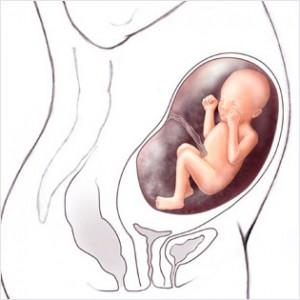

Bu haftadan itibaren artık bebek rahim içerisinde oldukça fazla yer kaplar ve bu yüzden ona hareket edecek fazla alan kalmaz. Eğer bebeğinizin hareketlerinde azalma his ederseniz endişe etmeyin, hareketlerin azalması bu yüzdendir.

Bebeğin Boyutu: 43.7 cm, 1.9 kg

Hamileliğin (Gebeliğin) 35. Haftası Resim ve Video;